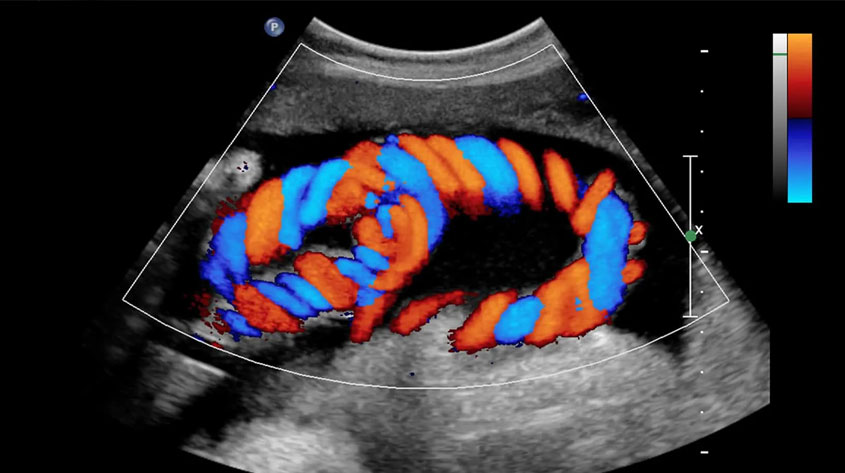

Color Doppler Ultrasound is an advanced diagnostic imaging technique that shows both the structure of organs and the direction, speed, and quality of blood flow inside blood vessels. By using color-coded imaging, it helps detect blockages, narrowing, abnormal flow patterns, and vascular problems in real time. This safe, painless, and radiation-free procedure is widely used in pregnancy, cardiology, and vascular assessments.